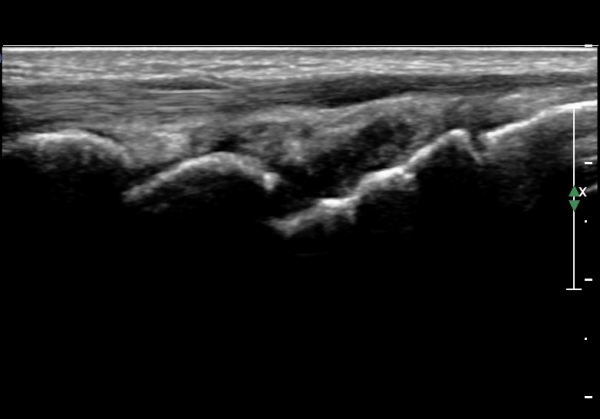

ÃÊÀ½ÆÄ°Ë»ç : ¼Õ¸ñ ¹èÃø Á¾´Ü¸é°Ë»ç¿¡¼­ ¼ö±Ù°üÀý³» ¼ö¾×Àú·ù°¡ °üÂûµÊ(»çÁø 1).